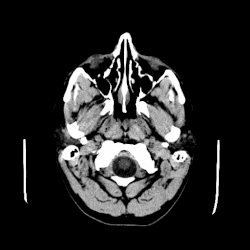

CT scan of a 1 cm colloid cyst